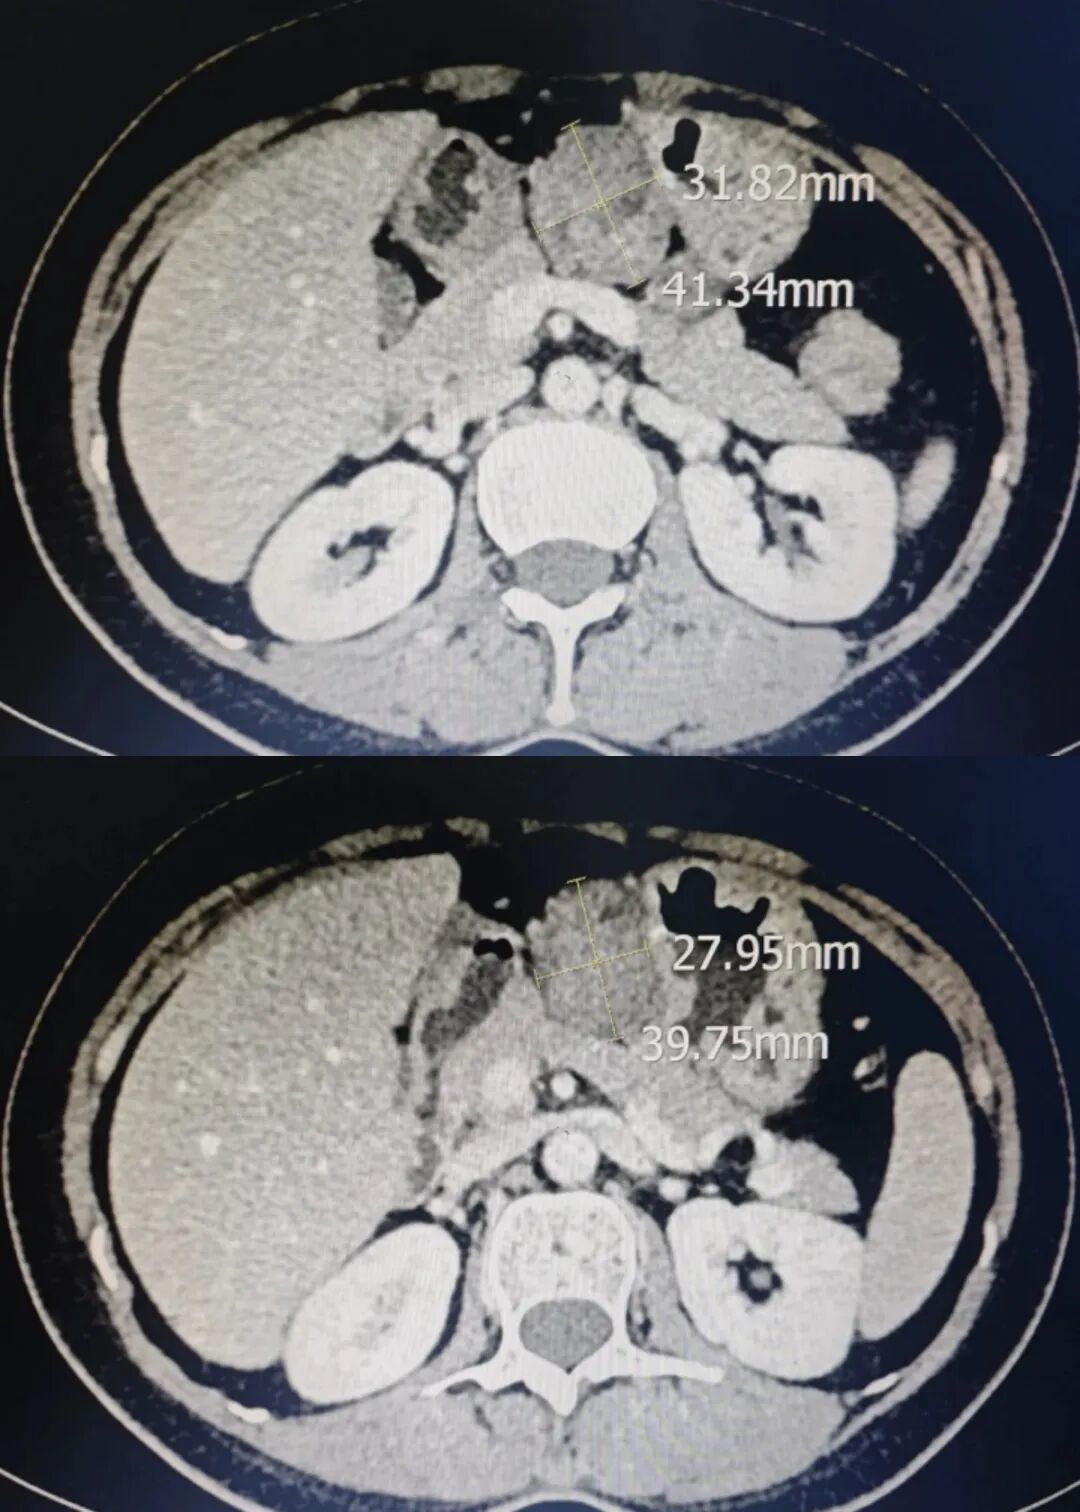

9 月 28 日,云南省曲靖中心醫(yī)院通過多學(xué)科協(xié)作(MDT)模式,由微創(chuàng)肝膽外科與婦科團隊主導(dǎo),醫(yī)學(xué)影像中心、麻醉科密切配合,成功實施曲靖地區(qū)首例 “NOSES(腹腔鏡下全子宮切除術(shù)+腹腔鏡下卵巢巧克力囊腫剝除術(shù)+腹腔鏡雙側(cè)輸卵管切除術(shù)+腹腔鏡下胃病損切除術(shù)+腹腔鏡下盆腔粘連松解術(shù),經(jīng)陰道取出標(biāo)本)手術(shù)”,標(biāo)志著醫(yī)院微創(chuàng)外科技術(shù)與多學(xué)科協(xié)作能力邁上新臺階。患者為一名46歲女性,因婦科癥狀就診,醫(yī)學(xué)影像中心經(jīng)精準(zhǔn)術(shù)前評估,不僅確診其患有多發(fā)性子宮肌瘤、卵巢巧克力囊腫,還同步發(fā)現(xiàn)胃竇部占位性病變。若采用傳統(tǒng)方案,此類多臟器病變需分兩次手術(shù),或單次手術(shù)留較大腹部切口取標(biāo)本,會顯著增加患者創(chuàng)傷與痛苦。為此,醫(yī)院啟動 MDT會診,微創(chuàng)肝膽外科、婦科、醫(yī)學(xué)影像中心、麻醉科專家共同研判后,決定為患者實施 “腹腔鏡下全子宮切除術(shù) + 卵巢巧克力囊腫剝除術(shù) + 雙側(cè)輸卵管切除術(shù) + 胃病損切除術(shù) + 盆腔粘連松解術(shù)(經(jīng)陰道取標(biāo)本)” 的多臟器 NOSES 聯(lián)合手術(shù)。患者術(shù)中生命體征平穩(wěn),術(shù)后各項指標(biāo)正常,恢復(fù)良好。NOSES 手術(shù)(經(jīng)自然腔道取標(biāo)本手術(shù))被譽為 “微創(chuàng)中的微創(chuàng)”,核心優(yōu)勢在于根治病變的同時,利用人體自然腔道取標(biāo)本,避免腹壁輔助切口。本次手術(shù)中,團隊先在腹腔鏡下精準(zhǔn)切除胃部病灶及婦科病變組織,再通過陰道完整取出標(biāo)本,患者腹部僅留數(shù)個微小操作切口。與傳統(tǒng)腹腔鏡手術(shù)相比,該術(shù)式優(yōu)勢顯著。創(chuàng)傷更?。簾o腹壁輔助切口,術(shù)后疼痛輕;恢復(fù)更快,患者下床活動早、腸道功能恢復(fù)快,可縮短住院時間;美容性佳,腹壁無明顯疤痕,更契合女性患者美觀需求;心理負(fù)擔(dān)輕,減少患者對手術(shù)疤痕的焦慮,提升就醫(yī)體驗。此次多臟器 NOSES 手術(shù)的成功實施,不僅是醫(yī)院在外科治療領(lǐng)域的一次重要突破 —— 它以 “更小創(chuàng)傷、更快恢復(fù)、更優(yōu)體驗” 的實踐,踐行了醫(yī)院對微創(chuàng)化、精準(zhǔn)化、人性化治療的長期追求,更生動展現(xiàn)了多學(xué)科協(xié)作的強大力量。未來,醫(yī)院將持續(xù)以患者需求為導(dǎo)向,加大新技術(shù)、新項目研發(fā)力度,進一步完善多學(xué)科協(xié)作機制,切實以技術(shù)創(chuàng)新守護群眾健康,為區(qū)域醫(yī)療事業(yè)高質(zhì)量發(fā)展注入源源不斷的動力。